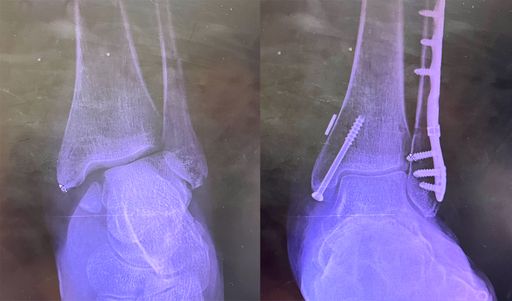

Last year, I broke my ankle after slipping on black ice outside my home, an abrupt moment that changed my sense of independence and control. A physical injury quickly became something more, impacting my mental health, my relationships, and my perception of time. Being confined to my couch for months created a sense of stillness that contrasted with the world around me. I felt stuck, as if life was continuing without me, and I was unable to catch up. My work reflects this experience of interruption and the emotional weight that followed. I am interested in how the body holds trauma and how spaces hold memory. The locations I document, my home, where the incident occurred, and my dorm, where I continue to recover, act as both physical and psychological environments. They reflect a transition between past and present, immobility and movement, isolation and reconnection.